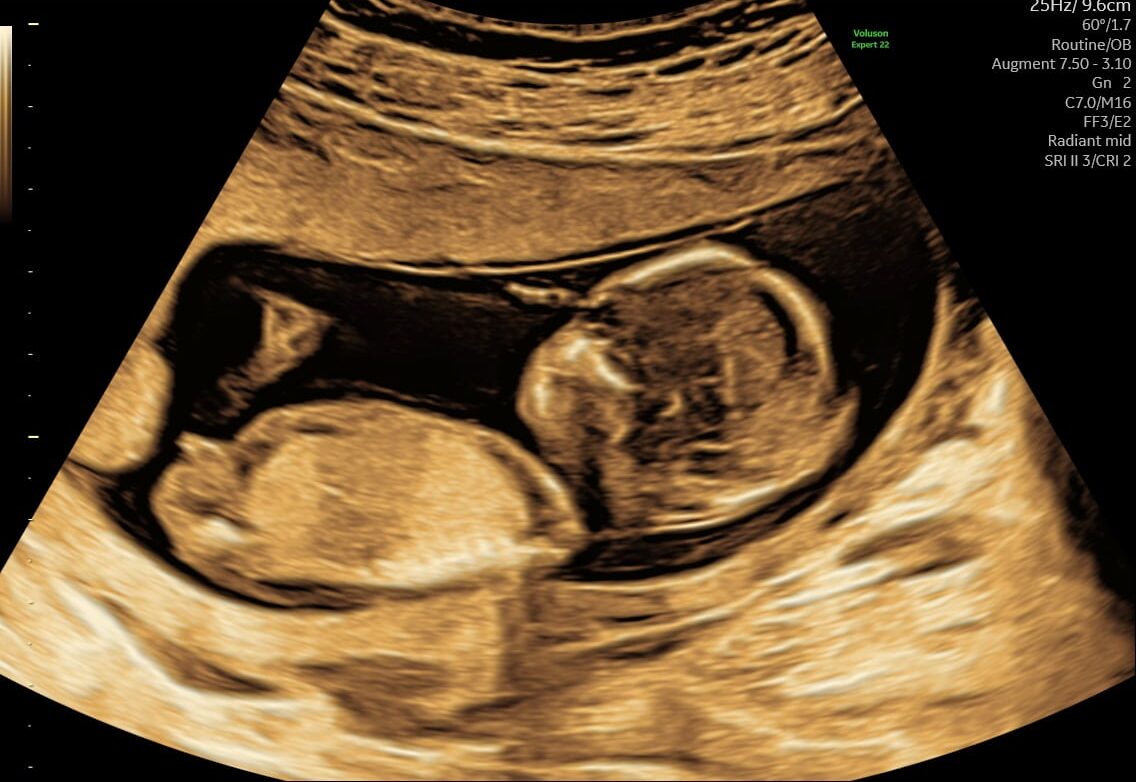

Mange kommende forældre glæder sig til at få at vide, om det er en lille dreng eller pige, der er på vej. Allerede fra uge 14+0 kan vi med en kønsscanning se barnets køn.

Kønsscanning afslører dit barns køn fra uge 14+0 – og du kan supplere med en 3D/4D scanning for at få detaljerede billeder.

Vores jordemoder kan se barnets køn helt fra uge 14 + 0. Hvilket man kan kalde en tidlig kønsscanning, og det giver dig og din partner rig mulighed for at forberede jer på den lille ny.

- Ved en kønsscanning hos praksisjordemoder får du en fin 2D kønsscanning af bedste kvalitet, hvor vi udover at se kønnet ser hjerteblink og lytter til det. Du kan se hvordan den lille ligger og bevæger sig, og det er tydeligt at se hvor hurtigt den lille udvikler sig i maven.

Udover at se kønnet er det bare så dejligt at få et lille ekstra kig ind til den lille på det her tidspunkt i graviditeten, de fleste mærker ikke liv endnu og der er stadig lidt tid til den næste scanning. Er du klar at vide om du skal have en lille dreng eller pige, så book en kønsscanning allerede i dag.